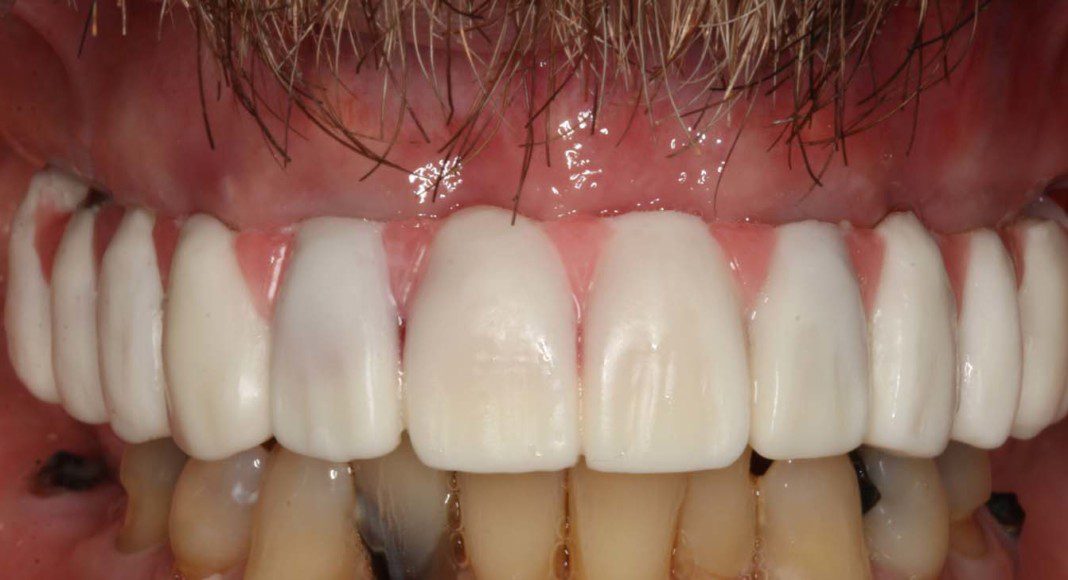

Mirror view of the tissues before delivery of the zirconia, implant bridge. Note the excellent volume of good, pink tissue (keratinized tissue). This good tissue is what allow the bone to remain healthy and full for many years if not forever.

Mirror view of final implant bridge. The screw holes have been sealed with composite resin. This plastic filling material can be easily removed to remove and clean or service the bridge. We call this “retrievability”.